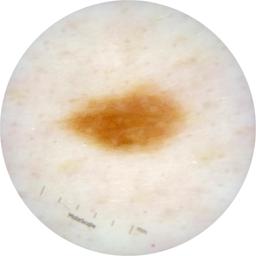

ISIC_9751750

2009 x 2009

acquisition_day 410

age_approx 50

anatom_site_1 Trunk

anatom_site_2 Posterior trunk

anatom_site_general posterior torso

diagnosis_1 Benign

diagnosis_confirm_type single image expert consensus

image_type dermoscopic